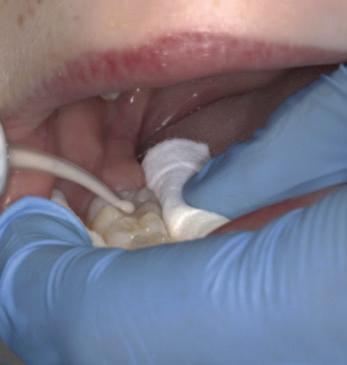

2. Wright, J.T., Crall, J.J., Fontana, M., Gillette, E.J., Nový, B.B., Dhar, V., et al Evidencebased clinical practice guideline for the use of pit-and-fissure sealants: a report of the American Dental Association and the American Academy of Pediatric Dentistry. J Am Dent Assoc 2016; 147 (8): 672-682.e12.

3. Lygidakis, N.A., Garot, E., Somani, C., Taylor, G.D., Rouas, P., Wong, F.S.L. Best clinical practice guidance for clinicians dealing with children presenting with molar-incisorhypomineralisation (MIH): an updated European Academy of Paediatric Dentistry policy document. Eur Arch Paediatr Dent 2022; 23 (1): 3-21.

4. Frencken, J.E. The state-of-the-art of ART sealants. Dent Update 2014; 41 (2): 119-120, 122-124.

CLINICAL TIPS

FIGURE 2: Effective cotton wool roll isolation. FIGURE 3: Conditioning of the pits and fissures. FIGURE 4a: Application of a GI sealant (GC Fuji IX). FIGURE 4b: Manipulation into the pits and fissures using the ‘finger press’ technique.

30 Journal of the Irish Dental Association | February/March 2023: Vol 69 (1)

FIGURE 5: GI fissure sealant.

A sagittal split osteotomy approach for removal of a large cementoblastoma at the mandibular angle

Précis

This case report demonstrates the effectiveness of sagittal split osteotomy in the removal of a mandibular cementoblastoma.

Abstract

Benign lesions at the angle of the mandible are frequently removed by a conventional intra-oral approach to gain access and achieve complete visualisation. This method is quick and effective when dealing with small, benign lesions that are superficially located at the angle of the mandible. The removal of large and deeply located lesions with a conventional intra-oral approach, however, brings about a unique set of challenges, particularly when the third molar is displaced towards the inferior border of the mandible, including: lack of complete visualisation of the lesion; difficulty in identification and protection of the inferior alveolar nerve; and, the necessity of removing a considerable amount of osseous structure, thus increasing the risk of a mandibular fracture. Alternative techniques for such lesions include an extra-oral approach, but this could potentially create a cosmetic defect from cutaneous scarring and can result in facial nerve injury.

This case report describes the use of a unilateral sagittal split osteotomy (SSO) in the removal of a mandibular cementoblastoma. This is a safe and effective technique allowing optimal access to the tumour with complete visualisation, identification and protection of the inferior alveolar nerve, and with minimal bone removal, while maintaining mandibular integrity, strength and facial aesthetics.

Introduction

A cementoblastoma, also referred to as a true cementoma, is a rare, benign odontogenic tumour arising from ectomesenchymal cells.1 They have also been referred to in the literature as: sclerosing cementoma; peri-apical fibroosteoma; and, peri-apical fibrous dysplasia. Disorganised proliferation of cementoblasts results in subsequent deposition of cement-like tissue around the roots of teeth. Cementoblastomas account for between 0.69% and 8% of all odontogenic tumours and tend to occur between the second and third decades of life, with a median age of 20 years and an age range of eight to 44 years. Some studies show no gender preference,2 while others show a higher rate of occurrence in males.3 Cementoblastomas tend to occur more frequently in the posterior mandible, involving the roots of premolar and

molar teeth. They are asymptomatic lesions, which demonstrate a slow and expansile growth, and are usually discovered as an incidental radiographic finding.4 However, cortical bone expansion can result in facial asymmetry and symptomatic painful lesions when facial nerves become involved.5 Because cementoblastomas have unlimited growth potential, treatment includes tumour resection with the extraction of the associated tooth. If the tumour is small at the time of diagnosis, treatment may consist of surgical removal with endodontic therapy and retention of the involved tooth. The traditional surgical approach for excision of a cementoblastoma at the mandibular angle is removal of bone to gain access to the tumour. However, the surgical risk increases with removal of larger lesions via traditional techniques, which will involve the removal of larger amounts of bone,

PEER-REVIEWED

Journal of the Irish Dental Association February/March 2023; 69 (1): 31-35

BA APsych BDS NUI MFD RCSI MB BCh BAO Surgical SHO

BDS

FFDRCSI

Registrar in Oral and Maxillofacial Surgery South Infirmary Victoria University Hospital Cork

FDS

in Oral and Maxillofacial Surgery South Infirmary Victoria University Hospital Cork Corresponding author: Dr Mar Cotter. E: mcottdentist@gmail.com Journal of the Irish Dental Association | February/March 2023: Vol 69 (1) 31

Dr Mar Cotter

Mr Zeeshan G. Khattak

MSc OMFS MFDS RCPS